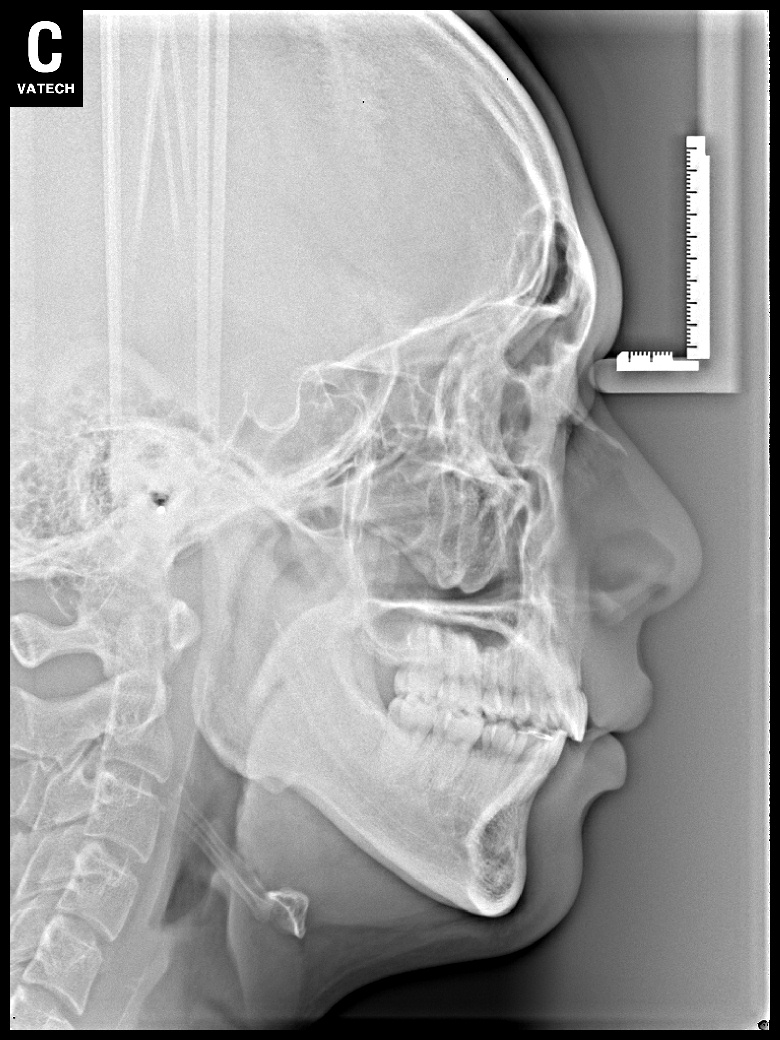

치료 전 사진입니다.